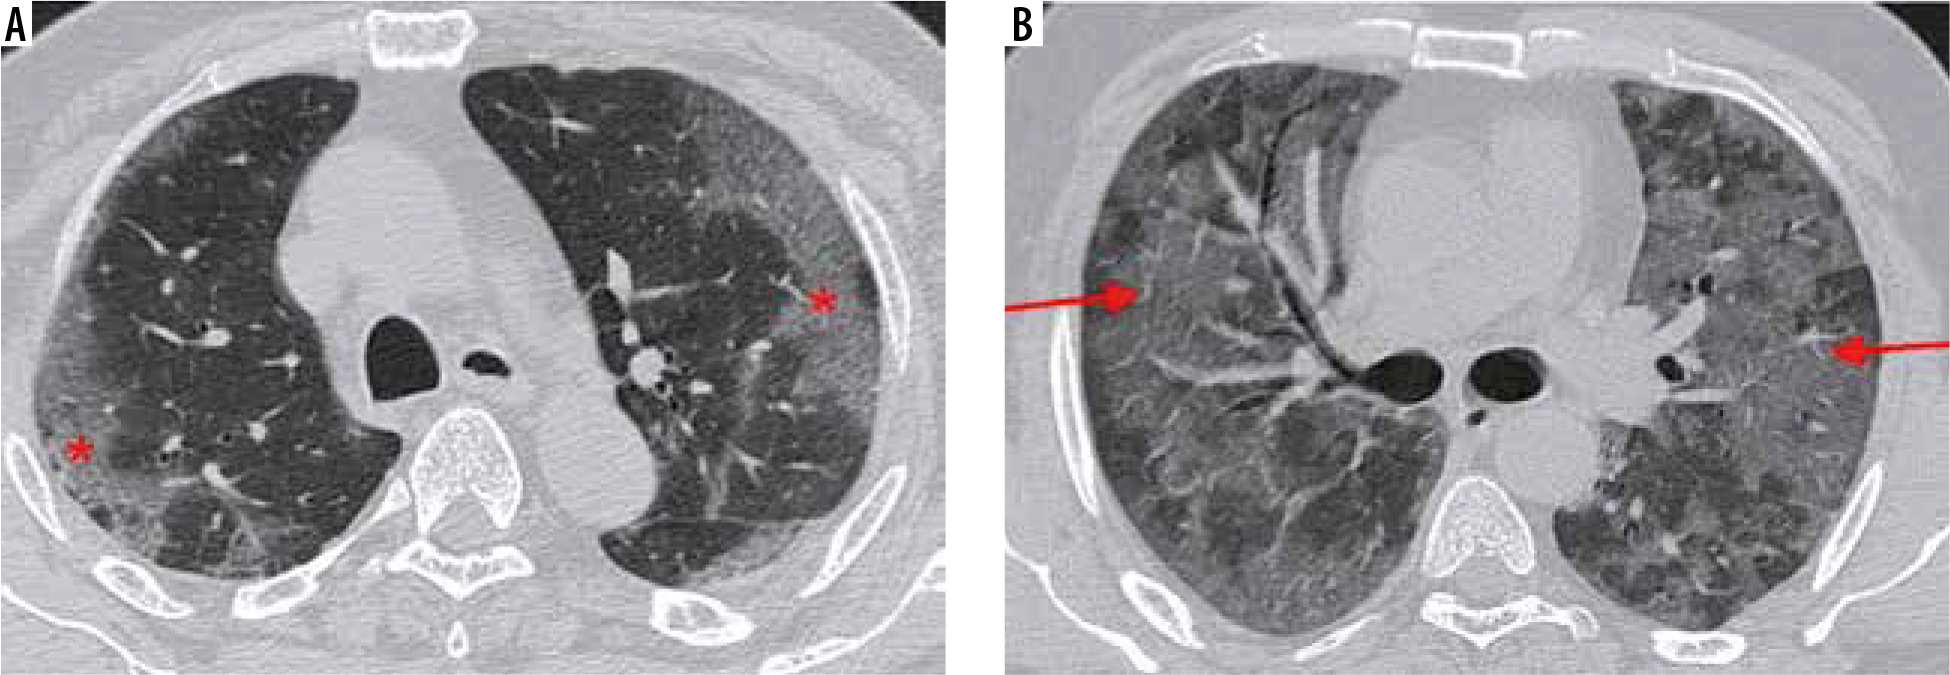

Atypical imaging features (Figure 18)

Figure 18

Atypical computed tomography (CT) chest findings in COVID-19 pneumonia. A) Axial chest CT image in a 32-year-old man in dissipative stage of disease shows an enlarged right paratracheal lymph node. B) Axial high-resolution computed tomography chest image in the same patient shows interlobular septal thickening with traction bronchiectasis and ground glass opacities suggestive of progression to interstitial lung disease. C-D) Axial chest CT images in 2 different patients with COVID-19 pneumonia show small subsolid nodules (red arrows)

The presence of pulmonary nodules, mediastinal lym-phadenopathy, and pleural effusions is rare in patients with COVID-19 [31]. At our institution, we have occasionally come across COVID-19 patients with enlarged mediastinal lymph nodes that could not be attributed to any other pathology (Figure 18A). A lymph node is classified as enlarged if it measures more than 10 mm in the short axis. Rare cases of COVID-19-positive patients with subsolid pulmonary nodules have also been observed (Figure 18C-D).